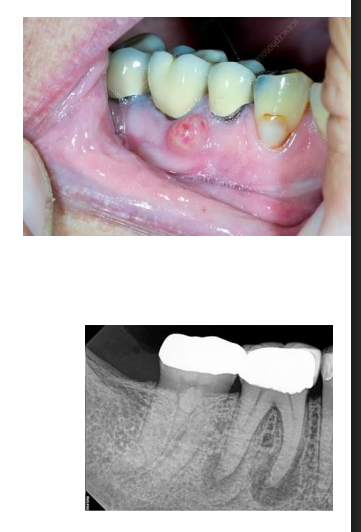

MFD EXAMS /23 6 1234567891011121314151617181920212223 You have 30 min to complete this exam. The timer will start once you begin Attention: Only a few minutes left! Please submit your answers soon. MFD 1 Get a quick sneak peek before the real exam !This trial quiz is designed to show you the question style, difficulty level, and how the options will appear on the platform. 1 / 23 1. What is the lethal dose and toxic dose of fluoride, management? Check 2 / 23 2. What the advantage of silver diamine over other methods and disadvantages ? Check 3 / 23 3. Method of topical fluoride application with concentration ? Check 4 / 23 4. What will happen if left untreated? Check 5 / 23 5. What changes that will happen if the habit stopped? Check 6 / 23 6. Give 3 of your initial stage of treatment? Check 7 / 23 7. What are the causes? Check 8 / 23 8. What is this? Check 9 / 23 9. Then they specified the type of pain and asked about the diagnosis Check 10 / 23 10. What other tests to check vitality of the pulp? Check 11 / 23 11. What are the factors will govern the Rx of Posterior cross bite ? Check 12 / 23 12. What are the factors that govern the treatment of anterior cross bite? Check 13 / 23 13. Name the appliance that you can use to treat this case? Check 14 / 23 14. Name 3 causes? Check 15 / 23 15. Name the most important clinical diagnostic information you need to know. (check RCSI intensive course )? Check 16 / 23 16. What do you see? Check 17 / 23 17. What is your treatment? Check 18 / 23 18. Name the investigations needed? Check 19 / 23 19. causes for gingival enlargement ? Check 20 / 23 20. What is the common side effect of this drug? Check 21 / 23 21. Name the drug that he may take to treat this condition? Check 22 / 23 22. The patient may have what? Check 23 / 23 23. What is this clinical condition? Check /31 2 12345678910111213141516171819202122232425262728293031 You have 30 min to complete this exam. The timer will start once you begin Attention: Only a few minutes left! Please submit your answers soon. MFD 2 Get a quick sneak peek before the real exam !This trial quiz is designed to show you the question style, difficulty level, and how the options will appear on the platform. 1 / 31 1. Mention 2 fixed space maintainers and 2 removable space maintainers other from mentioned : Check 2 / 31 2. Other space maintenance used for child lost primary second molar E before the eruption of the permanent molars ? Check 3 / 31 3. What are the difference between nance appliance and Transpalatal arch Check 4 / 31 4. What material used to attach band? Check 5 / 31 5. What instruction you give to patient? Check 6 / 31 6. Name other fixed space maintainer used in upper jaw and mechanism of their action? Check 7 / 31 7. What component of this appliance? Check 8 / 31 8. What is this appliance , for what its used ? Check 9 / 31 9. Treatment? Check 10 / 31 10. Define Abrasion and Erosion? Check 11 / 31 11. What does this picture show? Check 12 / 31 12. what investigations you can do ? Check 13 / 31 13. Drugs can lead to lichenoid reaction Check 14 / 31 14. What extra oral features in “ Lichenoid reaction )? Check 15 / 31 15. What microscopical features of it ( licheonoid reaction )? Check 16 / 31 16. Definitive diagnosis ? Check 17 / 31 17. Mention type of suggested biopsy ? Check 18 / 31 18. Mention 4 differential diagnosis ? Check 19 / 31 19. Mention 4 questions you will ask the patient ? Check 20 / 31 20. Give 4 intraoral decription of what you see ? Check 21 / 31 21. What the other surgery can be performed to make prothesis? Check 22 / 31 22. Can this tooth stand with fixed prothesis? (in the opg )à taken from Malek file ? Check 23 / 31 23. Radiograph of missing multiple teeth consider it according to Antes law? ON which tooth you will make Abutment ? Check 24 / 31 24. What is Antes law? Check 25 / 31 25. What is best one to use as abutment in fixed prosthesis A or B? Check 26 / 31 26. What relevance of this picture? Check 27 / 31 27. What’s complication of doing surgery in this area floor of mouth? Check 28 / 31 28. Other 2 radiograph needed in diagnosis? Check 29 / 31 29. Give 4 differential diagnosis? Check 30 / 31 30. What can you see ? Check 31 / 31 31. What is the name of radiograph? Check Your score is /30 1 123456789101112131415161718192021222324252627282930 You have 30 min to complete this exam. The timer will start once you begin Attention: Only a few minutes left! Please submit your answers soon. MFD 3 Get a quick sneak peek before the real exam !This trial quiz is designed to show you the question style, difficulty level, and how the options will appear on the platform. 1 / 30 1. Treatment? Check 2 / 30 2. Histopathology? Check 3 / 30 3. Differential diagnosis Check 4 / 30 4. Clinical features’? Check 5 / 30 5. Patient said, this lesion is very frequent, why? Check 6 / 30 6. What are the causes for ulcers? Check 7 / 30 7. Patient have other signs like uveitis ,Genital ulcerations which syndrome he had ? Check 8 / 30 8. Name of the lesion ? Check 9 / 30 9. Mention some TMJ movement ? Check 10 / 30 10. Blood supply ? Check 11 / 30 11. Nerve supply ? Check 12 / 30 12. Which muscles close? Check 13 / 30 13. Action of open and open wide? Check 14 / 30 14. Why it’s Atypical joint ? Check 15 / 30 15. Name of the ligaments ? Check 16 / 30 16. What would be your management? Check 17 / 30 17. Bacteria involved Check 18 / 30 18. Which type of Periodontitis? Check 19 / 30 19. Treatment? Check 20 / 30 20. Histopathology? Check 21 / 30 21. Differential diagnosis? Check 22 / 30 22. Clinical features? Check 23 / 30 23. What are the time frames for making a complaint? Check 24 / 30 24. What are the 3 points related to negligence? Check 25 / 30 25. Who is allowed access to the patient records? Check 26 / 30 26. How to differentiate if it is upper or lower motor neuron lesion? Check 27 / 30 27. Management? Check 28 / 30 28. What are the causes? Check 29 / 30 29. What should you advise the patient to do? Check 30 / 30 30. What is this lesion? Check Your score is /24 1 123456789101112131415161718192021222324 You have 30 min to complete this exam. The timer will start once you begin Attention: Only a few minutes left! Please submit your answers soon. MFD 4 Get a quick sneak peek before the real exam !This trial quiz is designed to show you the question style, difficulty level, and how the options will appear on the platform. 1 / 24 1. What does MRONJ stands for? Check 2 / 24 2. Give definition for MRONJ Check 3 / 24 3. For what medical problems these medications are used? Check 4 / 24 4. Stages of MRONJ 3 Check 5 / 24 5. What’s this appliance? Check 6 / 24 6. At what age is it used? Check 7 / 24 7. What type of malocclusion is it used to treat? Check 8 / 24 8. What changes will produce? (4 options) Check 9 / 24 9. Disadvantages? Check 10 / 24 10. Why is it flabby tissue? Check 11 / 24 11. what is this condition called? Check 12 / 24 12. Causes ? Check 13 / 24 13. Clinical Features ? Check 14 / 24 14. How to avoid it ? Check 15 / 24 15. Management? Check 16 / 24 16. Ideal post length and width Check 17 / 24 17. Definition of Ferrule it’s the Check 18 / 24 18. What is the importance of the ferrule effect ? Check 19 / 24 19. Describe the radiolucency? Check 20 / 24 20. Give 6 differential diagnosis? Check 21 / 24 21. Give 5 radiographical features? Check 22 / 24 22. What is the difference between incisional and excisional biopsy? Check 23 / 24 23. What other 2 plain radiographs we can we can take? Check 24 / 24 24. ALARA? Check Your score is /22 1 12345678910111213141516171819202122 You have 30 min to complete this exam. The timer will start once you begin Attention: Only a few minutes left! Please submit your answers soon. MFD 5 Get a quick sneak peek before the real exam !This trial quiz is designed to show you the question style, difficulty level, and how the options will appear on the platform. 1 / 22 1. . Types of external root resorption? Check 2 / 22 2. The cause of root resorption in the pic? Check 3 / 22 3. How you will treat it? Check 4 / 22 4. What is this probe? Check 5 / 22 5. What is the mark a ? Check 6 / 22 6. What is the mark b ? Check 7 / 22 7. What is the score from the given reading? Check 8 / 22 8. What is the treatment need of the patient according to the score? Check 9 / 22 9. What is the differential diagnosis ? Check 10 / 22 10. Four clinical features of the lesion? Check 11 / 22 11. Treatment ? Check 12 / 22 12. Describe what do you see? Check 13 / 22 13. Causes for it ? Check 14 / 22 14. Treatment ? Check 15 / 22 15. Picture of patient with Anaphylaxis…after taking Check 16 / 22 16. What is diagnosis? - Check 17 / 22 17. What a the signs of Anaphyalxis reactions ? Check 18 / 22 18. What first line of treatment? Dose? Route of Adminstration? Check 19 / 22 19. Other drug used? Check 20 / 22 20. What are expected complications if not treated ? Check 21 / 22 21. What precautions should be made to prevent anaphylaxis reaction ? - Check 22 / 22 22. Name 10 drug in emergency used with their route of Administration and their condition they use in? Check Your score is /36 1 123456789101112131415161718192021222324252627282930313233343536 You have 30 min to complete this exam. The timer will start once you begin Attention: Only a few minutes left! Please submit your answers soon. MFD 6 Get a quick sneak peek before the real exam !This trial quiz is designed to show you the question style, difficulty level, and how the options will appear on the platform. 1 / 36 1. . What are cases that you have to extract the primary tooth? Check 2 / 36 2. D. What are the indications for extraction? Check 3 / 36 3. What are your treatment options? Check 4 / 36 4. Investigations? Check 5 / 36 5. Type of trauma? Check 6 / 36 6. Patient diagnosed with sjorgen syndrome Histology ? - Check 7 / 36 7. Patient diagnosed with sjorgen syndrome Mention four blood investigations ? Check 8 / 36 8. Patient diagnosed with sjorgen syndrome Mention two sites where can we take the biopsy Check 9 / 36 9. Patient diagnosed with sjorgen syndrome How can you differentiate between primary and secondary ? Check 10 / 36 10. Gingival inflammation present in which syndrome Check 11 / 36 11. What is the treatment? Check 12 / 36 12. mention another connective tissue disease that can lead to lesions “ intraorally “ similar to the Lichen planus ? Check 13 / 36 13. what serious complication can arise from Erosive lichen planus ? Check 14 / 36 14. If it was atrophic lesion what histology might be seen ? Check 15 / 36 15. List the histological features of lichen planus ? Check 16 / 36 16. Lichen planus what dose it affect? Check 17 / 36 17. Age group commonly affected ? -ref SAQ Check 18 / 36 18. What are the clinical presentation ‘ types of lichen planus ‘ Check 19 / 36 19. What might you see in patient’s body that has a relation to this lesion? Check 20 / 36 20. What are the differential diagnoses? Check 21 / 36 21. Factors for platelet adhesion? Check 22 / 36 22. What can you see? Check 23 / 36 23. Other 2 process of hemostasis? Check 24 / 36 24. Two diseases in which they increase ? Check 25 / 36 25. Two diseases in which they decrease? Check 26 / 36 26. Medical term when they decrease? And if they increased Check 27 / 36 27. Function Check 28 / 36 28. Life span ? Check 29 / 36 29. From where they arise? Check 30 / 36 30. Normal number? Check 31 / 36 31. What are the function of the guiding plane ? Check 32 / 36 32. The success rate ? Check 33 / 36 33. Mention single extra preparation requirement for Resin bonded bridge in posterior teeth ? Check 34 / 36 34. Mention 5 preparation features of it? Check 35 / 36 35. Give two advantages of it ? Check 36 / 36 36. What’s the name of this prosthesis? Check Your score is /23 1 1234567891011121314151617181920212223 You have 30 min to complete this exam. The timer will start once you begin Attention: Only a few minutes left! Please submit your answers soon. MFD 7 Get a quick sneak peek before the real exam !This trial quiz is designed to show you the question style, difficulty level, and how the options will appear on the platform. 1 / 23 1. If the same scenario but the tooth is subluxated. What is the management? Check 2 / 23 2. Aim of this procedure Check 3 / 23 3. Steps to do this procedure? Check 4 / 23 4. Management? How to asses the vitality of the tooth Check 5 / 23 5. Mention factors that can affect the treatment plan ? Check 6 / 23 6. Identify the Kenneyd’s classification Check 7 / 23 7. Name its parts? Check 8 / 23 8. Uses of Surveyor Check 9 / 23 9. What is this ? Check 10 / 23 10. Criteria for hand piece sterilization Check 11 / 23 11. steps for wrapped instrument sterilization process ( ref : sterilization in SDCEP)? Check 12 / 23 12. What is the difference between sterilization and decontamination? Check 13 / 23 13. Optimal temperature & pressure & time for autoclave? Check 14 / 23 14. Difference between vacuum and non-vacuum autoclave in mechanism? Check 15 / 23 15. Optimum temperature? Check 16 / 23 16. Advantage of vaccum over non vaccum? Check 17 / 23 17. What is the significance of forehead wrinkling? Check 18 / 23 18. What is Ramsy haunt syndrome ? Rx ? and is it LMN or UMN ? Check 19 / 23 19. Enumerate 3 extracranial and intracranial causes for this ? Check 20 / 23 20. What are the branches of facial nerve? Check 21 / 23 21. Why do we suture the eye in a patient with Facial Palsy? Check 22 / 23 22. Differentiate between Upper and Lower Motor Neuron lesions? Check 23 / 23 23. What is shown in photograph? Check Your score is /27 0 123456789101112131415161718192021222324252627 You have 30 min to complete this exam. The timer will start once you begin Attention: Only a few minutes left! Please submit your answers soon. MFD 8 Get a quick sneak peek before the real exam !This trial quiz is designed to show you the question style, difficulty level, and how the options will appear on the platform. 1 / 27 1. Mention 4 diseases you would see in HIV Patients? Check 2 / 27 2. Give 2 differential diagnosis for this lesion? Check 3 / 27 3. Describe the lesion shown in Photograph B? Check 4 / 27 4. What is your diagnosis ? Check 5 / 27 5. Describe the lesion shown in Photograph A? Check 6 / 27 6. Disadvantages of gold ? Check 7 / 27 7. Ideal cement for All Porcelain? Check 8 / 27 8. Which cement would u use for high caries risk patient? Check 9 / 27 9. How much would you prepare for functional and non-functional cusps in Gold Crown? Check 10 / 27 10. what crown would you go for in bruxism patients out of these 3? Check 11 / 27 11. Name the 3 restorations? Check 12 / 27 12. After administering Local Anesthesia and deciding the choice of biopsy. What should be done before biopsying the lesion? Check 13 / 27 13. Name 2 systemic steroids with dosage you would recommend for this patient? Check 14 / 27 14. Name 2 topical steroids with dosage you would recommend for this patient? Check 15 / 27 15. What is your diagnosis? Check 16 / 27 16. Describe the lesion shown in photograph? Check 17 / 27 17. Name 5 options to increase retention and stability in class l Check 18 / 27 18. E. What is the function of the RPI system ? Check 19 / 27 19. What are the 2 disadvantages of the 2 restorations you mentioned? Check 20 / 27 20. What materials are your 2 restorations made of? Check 21 / 27 21. Other than implants what restoration would you place in this patient? Check 22 / 27 22. Which Kennedy’s classification is this? Check 23 / 27 23. Describe your management? Check 24 / 27 24. What may be the patient complaint? Check 25 / 27 25. What are the causes of this? Check 26 / 27 26. Describe what you see in the photograph? Check 27 / 27 27. which 4 examinations would you undertake? Check Your score is /31 0 12345678910111213141516171819202122232425262728293031 You have 30 min to complete this exam. The timer will start once you begin Attention: Only a few minutes left! Please submit your answers soon. MFD 9 Get a quick sneak peek before the real exam !This trial quiz is designed to show you the question style, difficulty level, and how the options will appear on the platform. 1 / 31 1. Describe what you see in the photograph? Check 2 / 31 2. Three other features of this syndrome ? Check 3 / 31 3. What is the medical condition associated with it “? Multiple OKC? Check 4 / 31 4. Where expansion occurs in the OKC ? Check 5 / 31 5. From which cells this lesion arises from? Check 6 / 31 6. What is your diagnosis? Check 7 / 31 7. What is the histopathology of the lesion shown in Histology slide? Check 8 / 31 8. Give 4 differential diagnosis? Check 9 / 31 9. What is the consequence of premature loss of deciduous teeth? Check 10 / 31 10. Identify those appliances and mention one use for each and mode of action? Check 11 / 31 11. What component of appliance no. 3 ? Check 12 / 31 12. How to overcome open bite disadvantage ? Check 13 / 31 13. What are Disadvantages of this appliance ? Check 14 / 31 14. What Ceph changes are expected while using this appliance ? Check 15 / 31 15. What is the construction of Twin Block Appliance? Check 16 / 31 16. What skeletal and dental changes are expected while using this appliance ? Check 17 / 31 17. What is the ideal age to treat this condition >? Check 18 / 31 18. Indications of the Twin Block Appliance? Two Check 19 / 31 19. Name the Appliance used to correct this? Check 20 / 31 20. What is the treatment? Check 21 / 31 21. How to prevent it Check 22 / 31 22. Mention three mechanisms of action of Fluoride? Check 23 / 31 23. What is the disease caused by excess Fluoride? Check 24 / 31 24. What are the risk factors associated with this patient? Check 25 / 31 25. Name the principal organism causing this? Check 26 / 31 26. what are the principles of the access cavity Check 27 / 31 27. What is your diagnosis? Check 28 / 31 28. What are principles of cavity preparation? Check 29 / 31 29. What is your Periapical diagnosis? Check 30 / 31 30. What is your Pulpal diagnosis? Check 31 / 31 31. Which test would you undertake? Check Your score is /21 0 123456789101112131415161718192021 You have 30 min to complete this exam. The timer will start once you begin Attention: Only a few minutes left! Please submit your answers soon. MFD 10 Get a quick sneak peek before the real exam !This trial quiz is designed to show you the question style, difficulty level, and how the options will appear on the platform. 1 / 21 1. Patient is 20 years old Mention two treatment options for this case ? Check 2 / 21 2. Patient is 20 years old What is the long term risk for not treating this case ? Check 3 / 21 3. Name of this appliance in the next picture? Check 4 / 21 4. What is the wire used ? Check 5 / 21 5. For which orthodontic cases this appliance is necessary ? Check 6 / 21 6. Why we use retainer ? Check 7 / 21 7. Describe what you see ? Check 8 / 21 8. Differential diagnosis:- Check 9 / 21 9. Name of those muscles ? Check 10 / 21 10. Name the Extrinsic muscles of the tongue? Check 11 / 21 11. . Which nerves innervate the Extrinsic muscles of the tongue?. Check 12 / 21 12. What is the somatic innervation of anterior 2/3 of tongue? Check 13 / 21 13. Which nerve supplies the posterior 1/3 of tongue?. Check 14 / 21 14. From which Pharyngeal arch posterior 1/3 derived from? Check 15 / 21 15. Mention the intrinsic muscle of the tongue ? Check 16 / 21 16. What is the name of this condition ? name the lesion on the skin ? Check 17 / 21 17. Mention 3 drugs that causing it ? Check 18 / 21 18. 2 infections associated with it Check 19 / 21 19. Mention 2 immediate treatment ? Check 20 / 21 20. Why this condition can be fatal ? Check 21 / 21 21. Which test would you undertake? Check Your score is